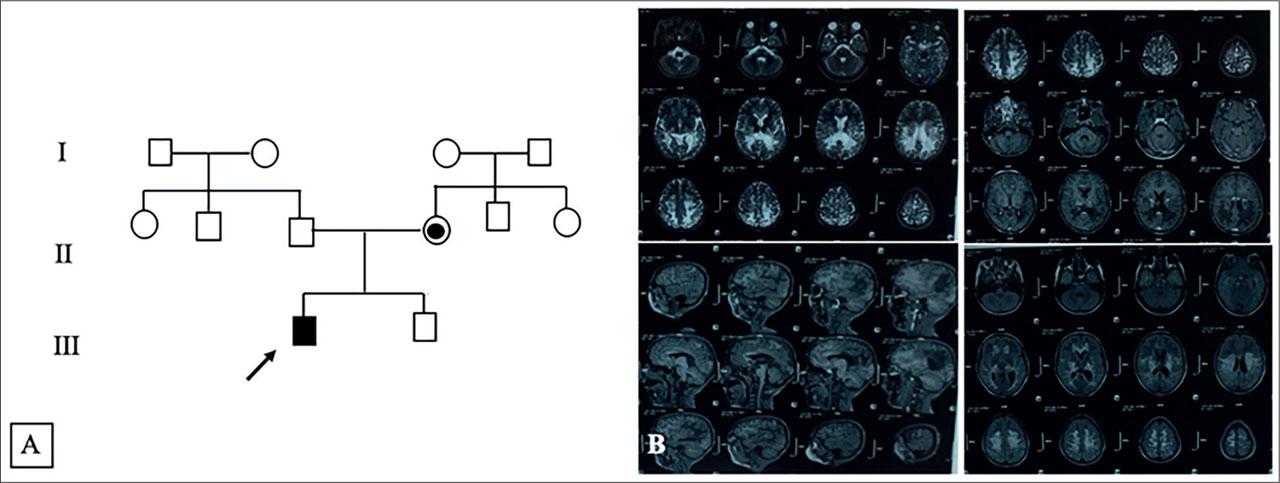

Figure 1.

| Cerebral involvement in MRI | Present |

| Spinal involvement in MRI | Absent |